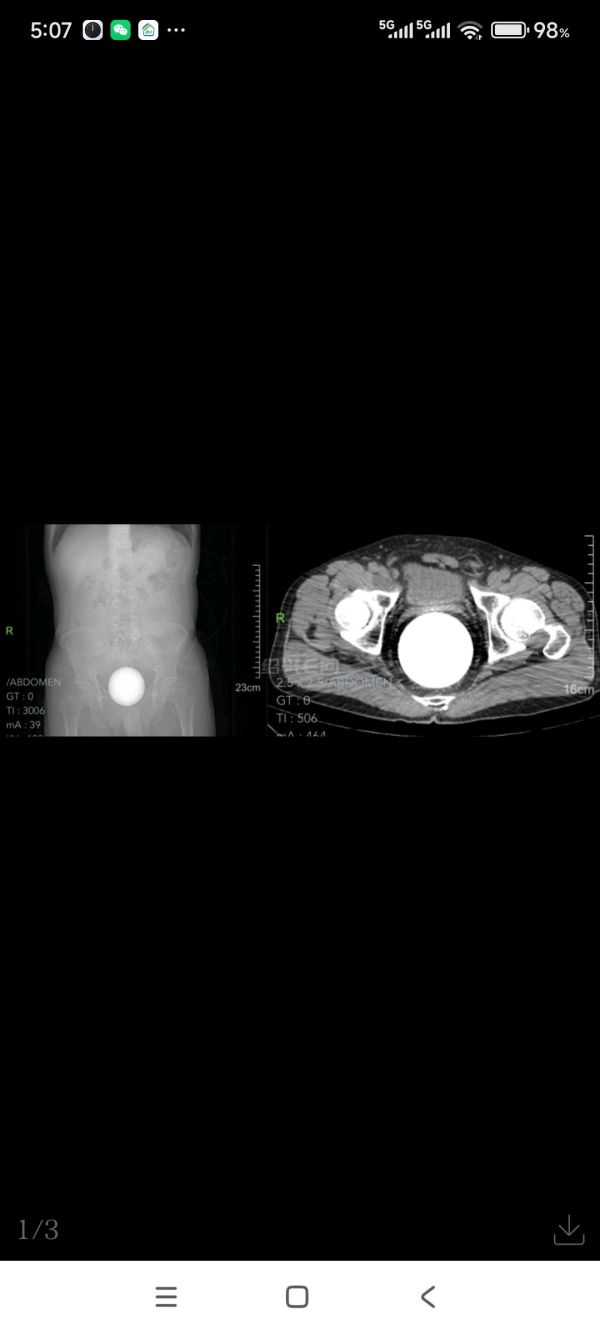

近日,浙江省人民医院越城院区急诊科迎来了一位特殊患者,其遭遇堪称“惊心动魄”——一枚直径9-10厘米的水晶球意外卡入直肠,导致患者肠腔堵塞、肛门会阴胀痛、大小便失禁。在辗转当地几家医院就诊后,患者为求无创技术取出体内水晶球遂来浙江省人民医院越城院区,面对这一棘手且危急的情况,该院迅速启动急诊绿色通道,展开了一场生命与时间赛跑的紧急救援。

事发突然,患者痛苦不堪且腹胀等肠梗阻症状逐渐显现,每一秒都关乎着生命的安危。浙江省人民医院肛肠外科柴瑞主任团队立即响应急诊召唤,以最快的速度将患者送入手术室。此时,玻璃球已深深嵌入直肠壶腹部,周围组织脆弱敏感,稍有不慎便可能引发更大继发性损伤。如何用最微创的手术方式把无处着力的巨大水晶球完整从体内取出考验着在场的所有医务工作者,团队中柴瑞主任及万子昂副主任迎难而上,他们凭借丰富的临床经验和精湛外科微创手术技能,手术台上反复小心翼翼探查异物情况及不断地校准手术方案。

经过紧张而有序的麻醉及手术,这颗“定时炸弹”终于被“带有钢丝套圈性质的取物带”非直视下经肛成功套进并顺利取出,整个手术过程高效顺畅,从接诊到异物取出,仅用了1小时,患者避免了被开肠破肚,整个水晶球取出的那一刻手术室内所有医生、护士和麻醉师发出阵阵欢呼声,大家一致认为只要不开肠破肚该手术就堪称绝对完美。术后患者恢复良好,48小时内康复出院,对医护人员的专业技能与救治速度赞不绝口。同时该患者本次就诊流程也充分展现了该院急诊绿色通道的高效与实力。

直肠虽叫直肠,但它并不直,它有2个弯曲(骶曲、会阴曲)。加之肛门括约肌受到刺激后会收缩、关闭,使得进入肛门的异物进易出难。如果异物停留时间过久则会造成更严重的并发症,诸如肠梗阻、肠坏死及肠穿孔等症,所以一旦有异物进入需马上就医。